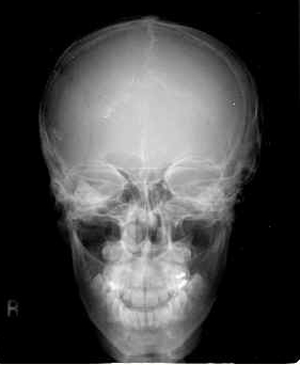

수막종 (Meningioma)

국한성 hyperosteosis를 초래하는 가장 많은 질환

우선적으로 내판을 침범 - 두께와 변연의 윤곽을 주의깊게 관찰

진행시 판간층(diploe)에도 hyperosteosis가 일어나 용이하게 인식

X-선 소견

hyperosteosis( 과골증 )

erosion

혈관구(vessel sulcus)의 확대

석회화(calcification)